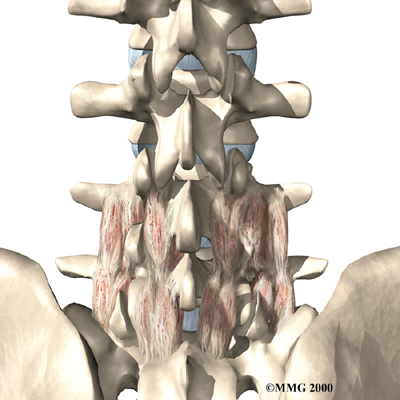

Posterior Lumbar Fusion

Lumbar disc herniation causes mechanical pain, the type of pain caused by wear and tear in the parts of the lumbar spine. Fusion surgery is mainly used to stop movement of the painful area by joining two or more vertebrae into one solid bone. This keeps the bones and joints from moving, easing mechanical pain.

In posterior lumbar fusion, the surgeon lays small grafts of bone over the problem area on the back of the spinal column. Most surgeons will also apply metal plates and screws to prevent the problem vertebrae from moving. This protects the graft so it can heal better and faster.

Related Document: FYZICAL South San Antonio's Guide to Posterior Lumbar Fusion